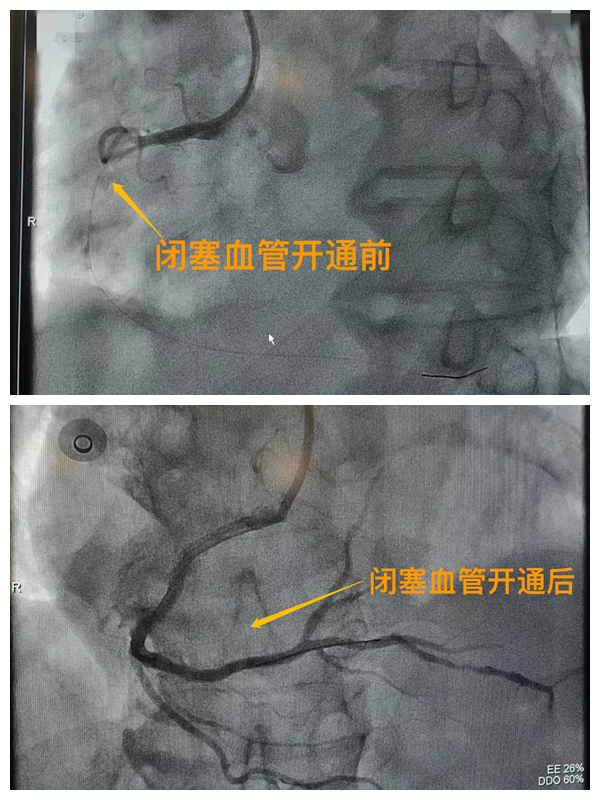

活動開始前,院長王瑾對現(xiàn)場群眾進(jìn)行了健康科普宣講,她以近期醫(yī)院救治的多例急性心肌梗死患者的癥狀、發(fā)展、急救、手術(shù)、康復(fù)全流程情況為例,向小區(qū)群眾講述了心梗的發(fā)病癥狀和院前急救注意事項,以及要及時通過120送至專業(yè)的胸痛中心開展科學(xué)、規(guī)范的急救手術(shù)的必要性,講述了心?;颊咿D(zhuǎn)危為安的全過程,得到了廣大群眾的共鳴與好評。

市二院胸痛中心于2021年12月23日通過中國胸痛中心認(rèn)證,成為國家級胸痛中心,先后開展了冠心病的介入診療、心律失常的心內(nèi)電生理檢查及射頻消融治療、永久起搏器植入、先天性心臟病的介入封堵及臨時起搏器植入、主動脈內(nèi)球囊反搏治療等,完成心臟介入手術(shù)3000余例。多次創(chuàng)造從入院至行急診介入手術(shù)開通血管(入門-導(dǎo)絲通過)30分鐘以內(nèi)記錄,極大保證了患者的生命安全,提高了預(yù)后質(zhì)量,挽救了眾多急性心?;颊叩纳?span style="text-align: right;">(尹紅婭       張   靜)